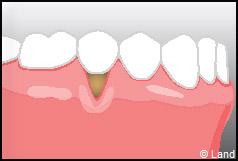

Les conséquences de cette mise à nu de la racine dentaire sont multiples, le patient peut présenter une hypersensibilité dentaire et l’aspect de ces récessions peut être inesthétique. Dans ce cas, la chirurgie muco-gingivale est recommandée et elle peut se faire de différentes façons.

Les greffes épithélio-conjonctives :

Elles sont pratiquées pour des zones non esthétiques de la cavité buccale, à cause de l’aspect « rustine» que la cicatrisation leur confère.

Destinées aux zones esthétiques, elles consistent à prélever la partie profonde du palais (site donneur).